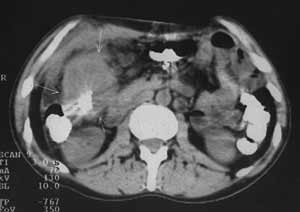

Рис. 1. Рак печеночного угла толстой кишки: неравномерное утолщение стенки кишки, ее неоднородность, инфильтрация окружающей клетчатки, утолщение близлежащего участка брюшины.